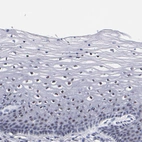

Immunohistochemical staining of human rectum shows moderate positivity in nuclear speckles in glandular cells.